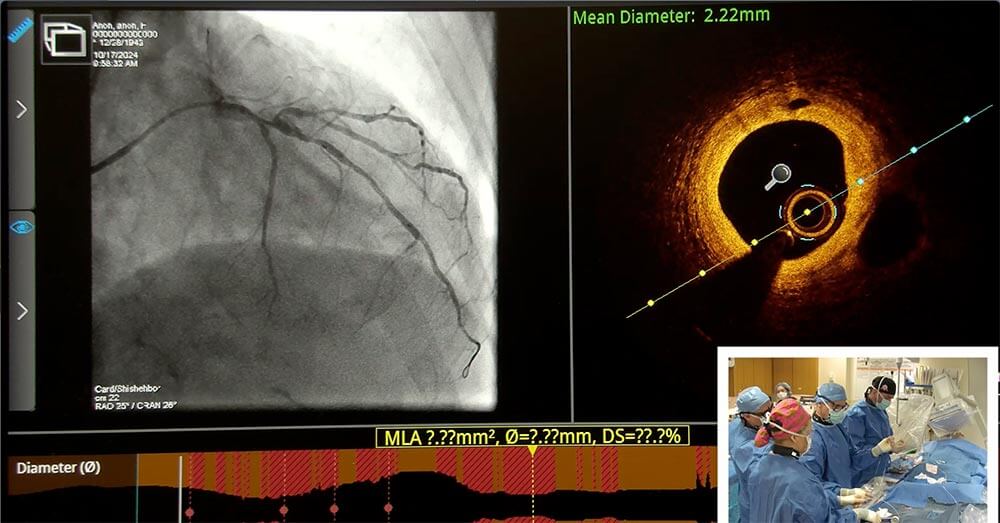

- Stent optimization techniques including intracoronary imaging